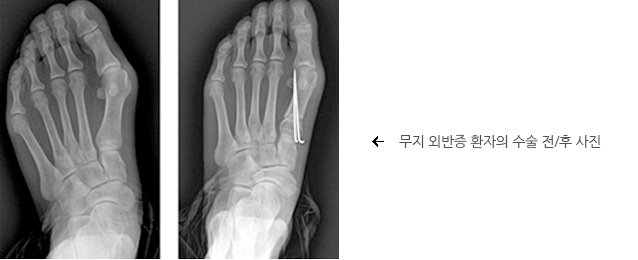

무지 외반증

동통이나 변형이 심한 중등도 이상의 변형의 경우, 또는 보존적 치료에도 신발을 신기 어려울 정도의 일상생활에 지장이 있는 경우라면 수술적 치료의 대상이 됩니다. 수술을 통해서 훨씬 보기 좋고 안 아픈 발로 만들 수 있고 수술의 후유증이나 재발은 매우 적기 때문에 많이 사용되고 있습니다 경증의 무지 외반증의 경우에는 중족골의 원위부에서 절골하는 원위부 갈매기 절골술을 단독으로 시행하거나 근위 지골 절골술을 병행하여 시행할 수 있습니다. 경증이거나 중등도의 무지 외반증의 경우 원위, 중위, 근위중족골 절골술중 하나와 원위부에서 연부 조직의 재정렬을 위한 수술을 같이 시행할 수 있고, 중증의 무지 외반증의 경우는 원위 연부 조직 수술과 더불어 중위나 근위에서 중족골의 절골술을 시행합니다